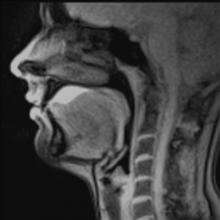

Swallowing, sometimes called deglutition in scientific contexts, is the process in the human or animal body that makes something pass from the mouth, to the pharynx, and into the esophagus, while shutting the epiglottis. Swallowing is an important part of eating and drinking. If the process fails and the material (such as food, drink, or medicine) goes through the trachea, then choking or pulmonary aspiration can occur. In the human body the automatic temporary closing of the epiglottis is controlled by the swallowing reflex.

Eating and swallowing are complex neuromuscular activities consisting essentially of three phases, an oral, pharyngeal and esophageal phase. Each phase is controlled by a different neurological mechanism. The oral phase, which is entirely voluntary, is mainly controlled by the medial temporal lobes and limbic system of the cerebral cortex with contributions from the motor cortex and other cortical areas. The pharyngeal swallow is started by the oral phase and subsequently is co-ordinated by the swallowing center on the medulla oblongata and pons. The reflex is initiated by touch receptors in the pharynx as a bolus of food is pushed to the back of the mouth by the tongue, or by stimulation of the palate (palatal reflex).

Swallowing is a complex mechanism using both skeletal muscle (tongue) and smooth muscles of the pharynx and esophagus. The autonomic nervous system (ANS) coordinates this process in the pharyngeal and esophageal phases.